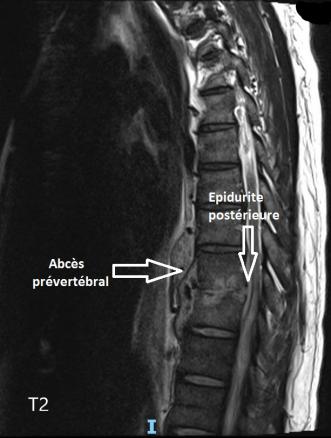

Spondylodiscite, abcès prévertébral antérieur, épidurite postérieure

IRM rachidienne, coupe sagittales, séquence T2